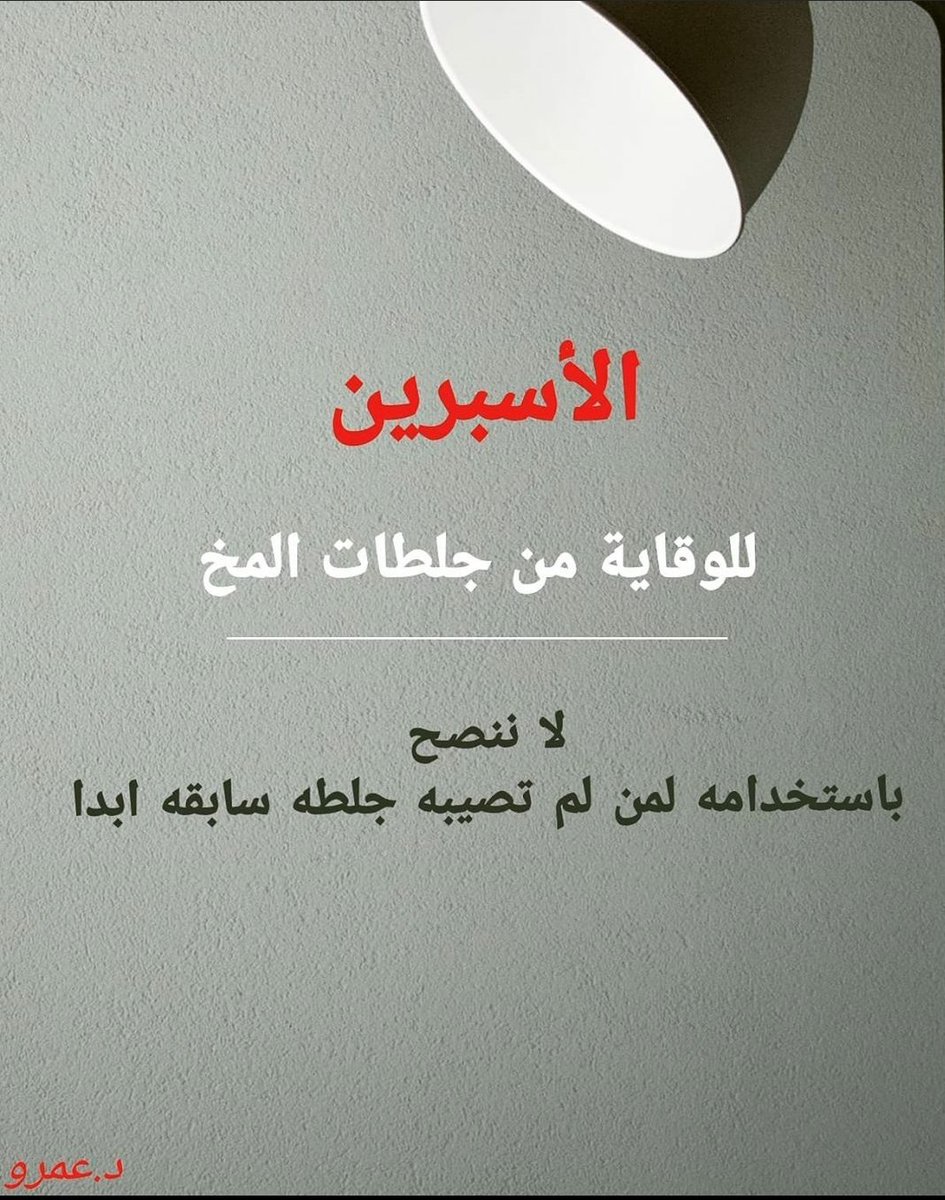

معلومات توعويه مفيدة عن #الاسبرين و #السكته_الدماغيه

💥بشكل عام

🧠لايستخدم الابتوجيه الطبيب

🧠لم تؤيد الدراسات استخدامه لمن لم يصاب بجلطه سابقه

🧠الاصل علاج سيوله صحيح واحد يكفي إلا حالات نادرة قد نحتاج اكثر

💥بشكل عام

🧠لايستخدم الابتوجيه الطبيب

🧠لم تؤيد الدراسات استخدامه لمن لم يصاب بجلطه سابقه

🧠الاصل علاج سيوله صحيح واحد يكفي إلا حالات نادرة قد نحتاج اكثر